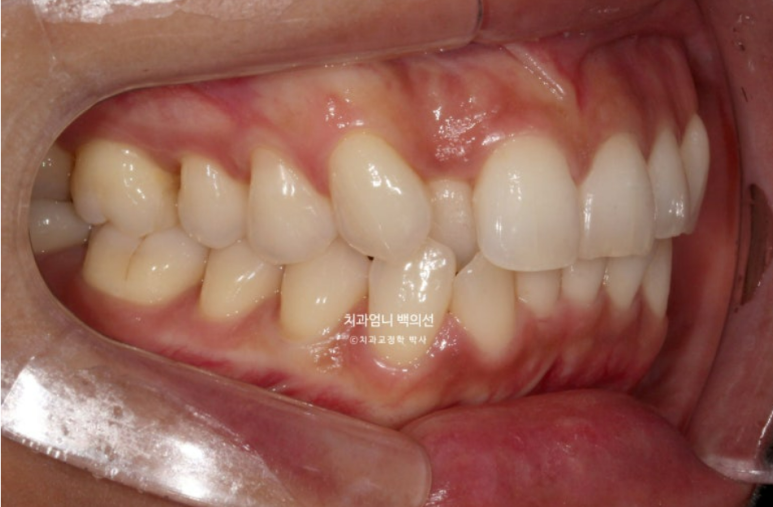

덧니가 심하고 입이 잘 안다물어 지기는 하지만 입매 분석시 입술 돌출이 없어서 작은어금니 발치는 하지 않았습니다.

대신 사랑니 공간이 충분해서 사랑니 공간으로 어금니 후방이동을 통해 덧니를 배열하기로 합니다.

어금니 후방이동에 교정용 나사인 미니스크류는 꼭 필요합니다.

여담으로 앞니 반대교합이 해소되는 과정에서는 대합치와 엉킨부분이 풀리는 과정에서 서로 먼저 닿는 조기첩촉 시기가 있습니다.

중간 과정상 불가피한 부분이지만 이 시기에는 먼저 닿아 어금니가 잘 안 닿고 해당치아끼리 자주 부딪쳐 불편합니다.

아래치열은 더 이상 고칠 것이 없어보입니다.